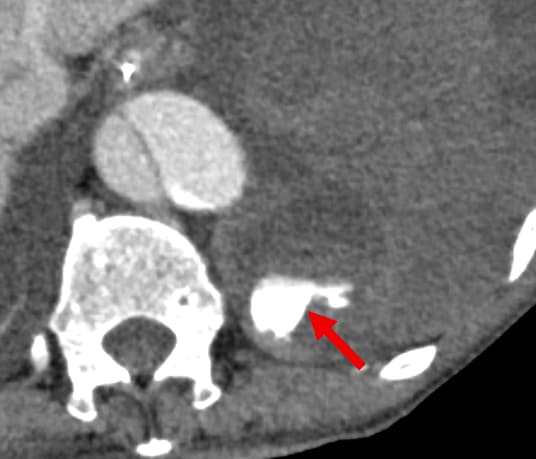

背景として、5年前に急性大動脈解離に対し全弓部置換術を施行されており、1か月前に人工血管感染のため開胸ドレナージおよび緊急予防的TEVARが施行されている。その1週間後、待機的に再全弓部置換術および大網充填が施行された。手術は問題なく終了したものの、術後9日に創部皮下の血腫を認めた。術後12日には胃管からの黒色排液や貧血の進行が認められ、上部消化管内視鏡検査が施行されたが活動性出血は指摘できず、出血源精査のため造影CT検査が施行された。左第11肋間動脈より活動性出血の所見があり、緊急的TAEを施行した。その後貧血の進行なく経過している。

今回の症例は、術後にある程度の日数が経過してから貧血の進行が顕在化していた。術直後から左胸水の増加が緩徐であったことや胃管から黒色排液を認めたことから、まず上部内視鏡検査が施行され、胸腔内の出血は積極的に疑われていなかった。実際、後方視的にも今回のCT以外では血胸を認めず、高頻度に撮影されていた胸部単純写真(臥位)では有意な変化は認められていなかった。そこで今回の撮像では胸部~骨盤部にかけて広範囲の活動性出血の検索が目的となっている。早期動脈相により動脈性の出血が同定でき、後期相の撮像により仮性動脈瘤等との鑑別も可能になっている。また、非造影検査により血性胸水の同定や石灰化と濃染域との鑑別も容易になっている。薄層やMPRの画像も作成されており責任血管の同定がしやすくなるとともに、治療(TAE)の一助にもなっている。